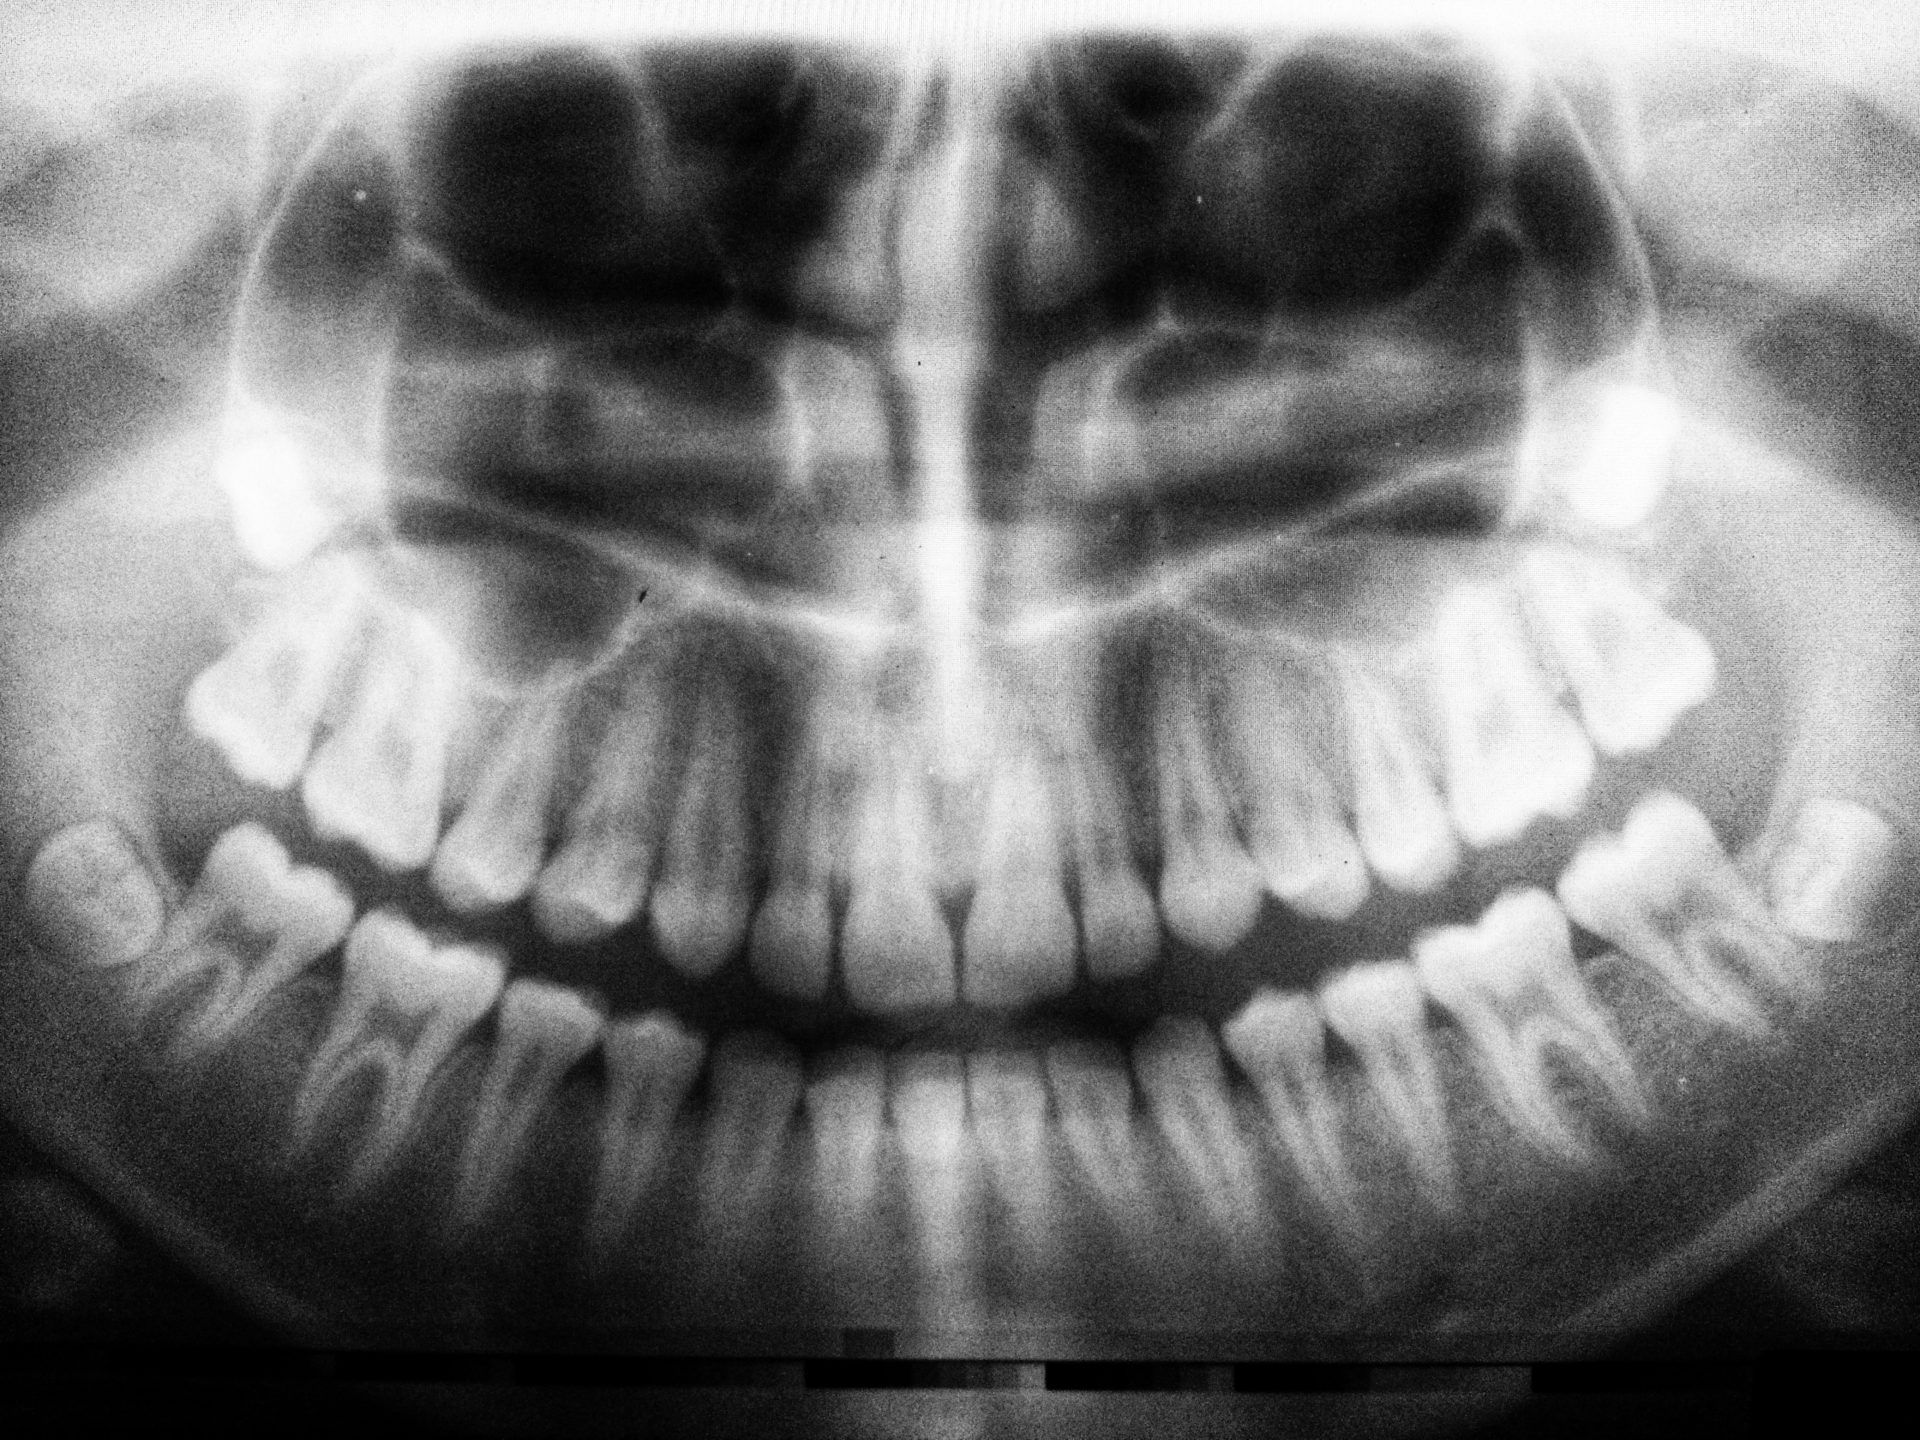

TMD involves an injury to the temporomandibular joints (“TMJ”). The TMJ is the hinge where your jaw connects to your skull on both sides of your head. This joint is extremely flexible and allows for movement up and down and side to side. The TMJ is comprised of muscles, blood vessels, nerves, and bones.

The TMJ are required for talking, chewing, and yawning. Pain in these joints can significantly impact an individual’s life by leading to chronic facial pain, joint pain, earaches, and headaches. This pain may be temporary for some, or can last for years for others.